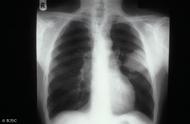

更多健康内容不再错过,不定期惊喜送给你目前肺癌的发病原因基本明确,除吸烟以外,还有大气污染、职业因素、肺部慢性疾病、遗传及免疫力等多方面原因。